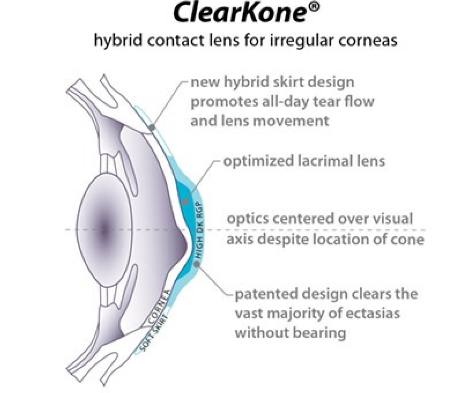

Een kleine greep uit ons aanbod